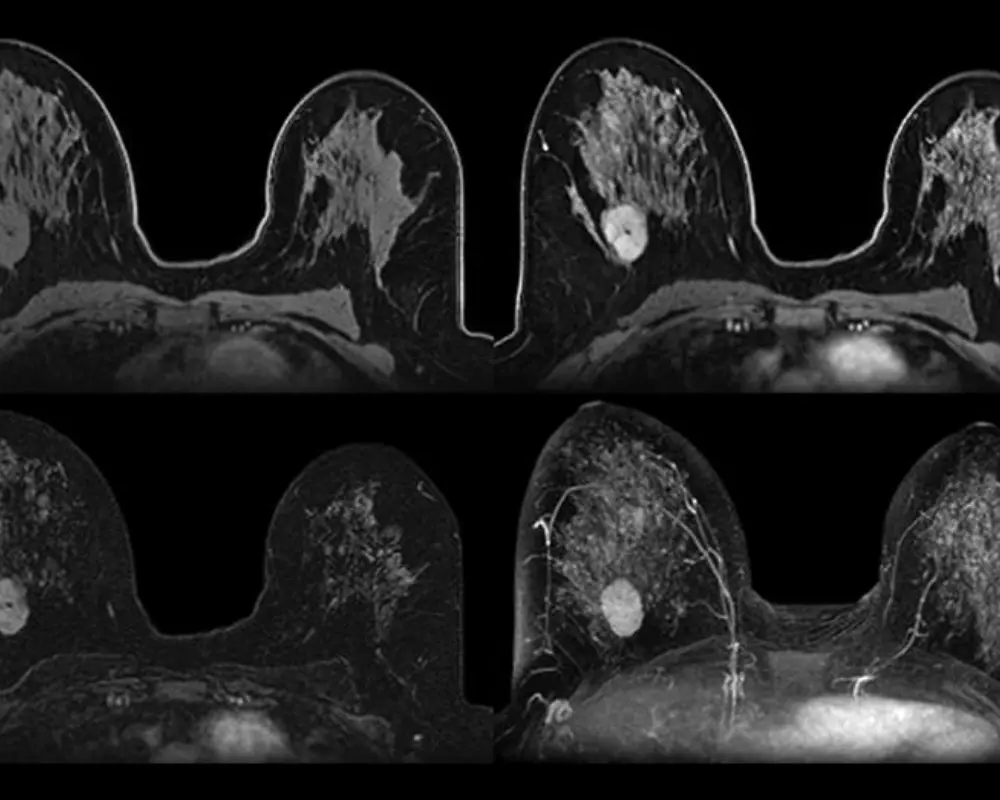

Breast MRI is a highly detailed imaging method used to examine breast tissue more closely than standard imaging. It is often recommended when additional clarity is needed, especially in cases involving dense breast tissue or areas that require further evaluation.

Breast MRI is often recommended when a more detailed view of breast tissue is needed beyond standard imaging. It provides deeper insight into areas that may not be clearly visible on a mammogram or ultrasound, especially when further evaluation is required.

At Maximum Resolution Imaging Center, our breast MRI in Houston TX and Richmond TX helps detect conditions such as breast lesions, abnormal tissue changes, implants evaluation concerns, and areas that may require closer examination. This advanced imaging supports early detection and helps guide the next steps in care with greater clarity and confidence.

Breast MRI helps detect breast cancer by identifying abnormal tissue changes and small lesions. It provides detailed imaging that supports early diagnosis, especially when other tests do not show clear results.

Breast MRI is commonly used for dense breast tissue evaluation, where mammograms may be less effective. It helps provide clearer imaging and improves detection of abnormalities that might otherwise go unnoticed.

Breast MRI with contrast enhances image clarity by highlighting blood flow and abnormal areas. It helps improve detection of suspicious tissue and supports more accurate diagnosis during detailed breast MRI examinations.

Breast MRI provides highly detailed images of breast tissue, helping identify abnormalities that may not be visible through other imaging methods. It supports accurate diagnosis and better evaluation.